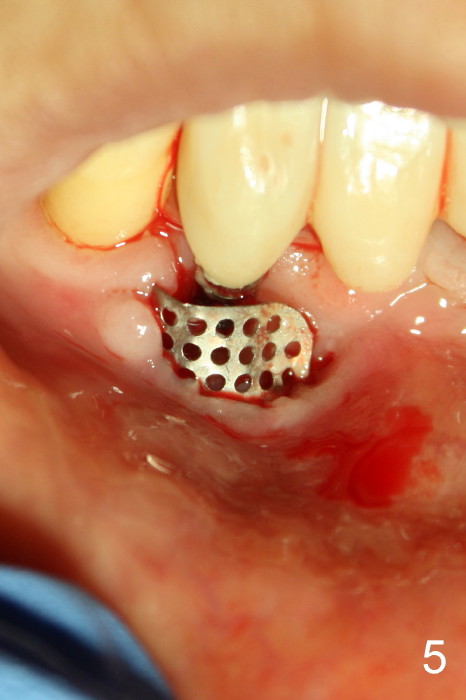

The coronal portion of the mesh is exposed with loss of bone graft granules. It appears that the mesh has lost its function. It is planned to be removed. PA is taken 16 days post placement of the mesh (Fig.4).

Fig.5 is taken following local anesthesia to show the exposed mesh, 22 days post placement. When the latter is removed, the exposed threads appear to be less (Fig.6, as compared to Fig.2). There is healthy granulation tissue growth apically (*). The patient is asymptomatic 1 month post mesh removal; there is no tenderness around exposed threads (Fig.7). Connective tissue graft is planned to cover the exposed threads through tunnel technique. Thread exposure appears less 3 months post mesh removal (Fig.8). There is infection when the region is not kept clean (Fig.9 (2.5 years post mesh removal)). The other 1-piece implant should have minor implant exposure (<). It appears that there is no thread exposure associated with the immediate implant at #28. Using smaller 1-piece implants (2.5 or 2.0 vs. 3 mm) with flap surgery should be able to prevent the complication. The 72-year-old phobic patient declines any further treatment. Two years later, she agrees to have treatment because of repeated infection (Fig.10). Impression has been taken for stent. After sectioning FPD and removing the infected implant (Tatum), a smaller implant will be placed in between the implants. If her vein is not too small, blood will be drawn for PRF.